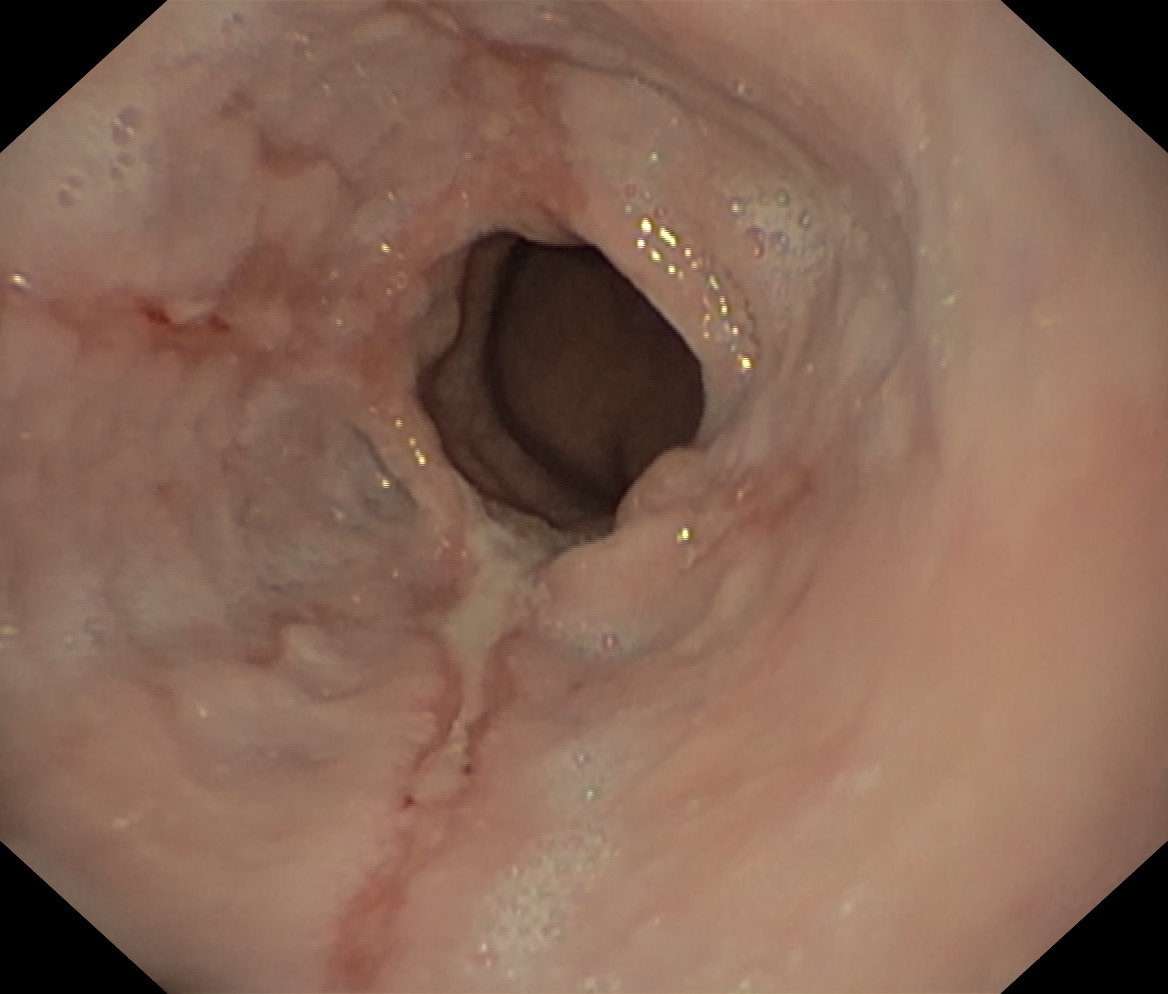

Choroba refluksowa